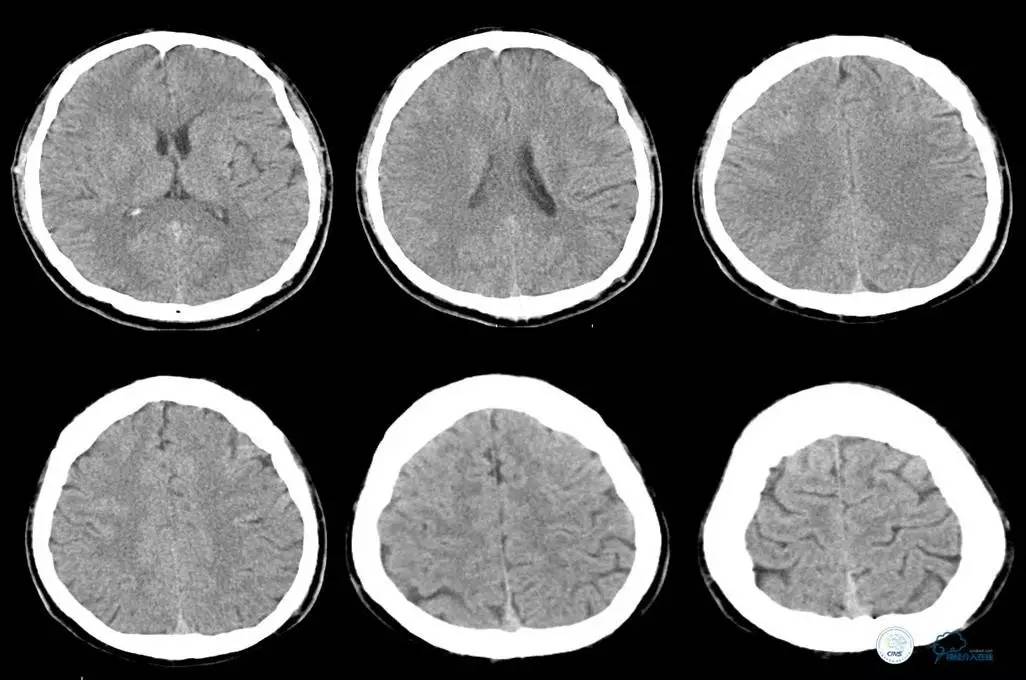

辅助检查:头CT未见异常。

初步诊断:

脑梗死——右颈内动脉系统

胸闷、胸痛待查,主动脉夹层?

治疗原则:急查主动脉CT。